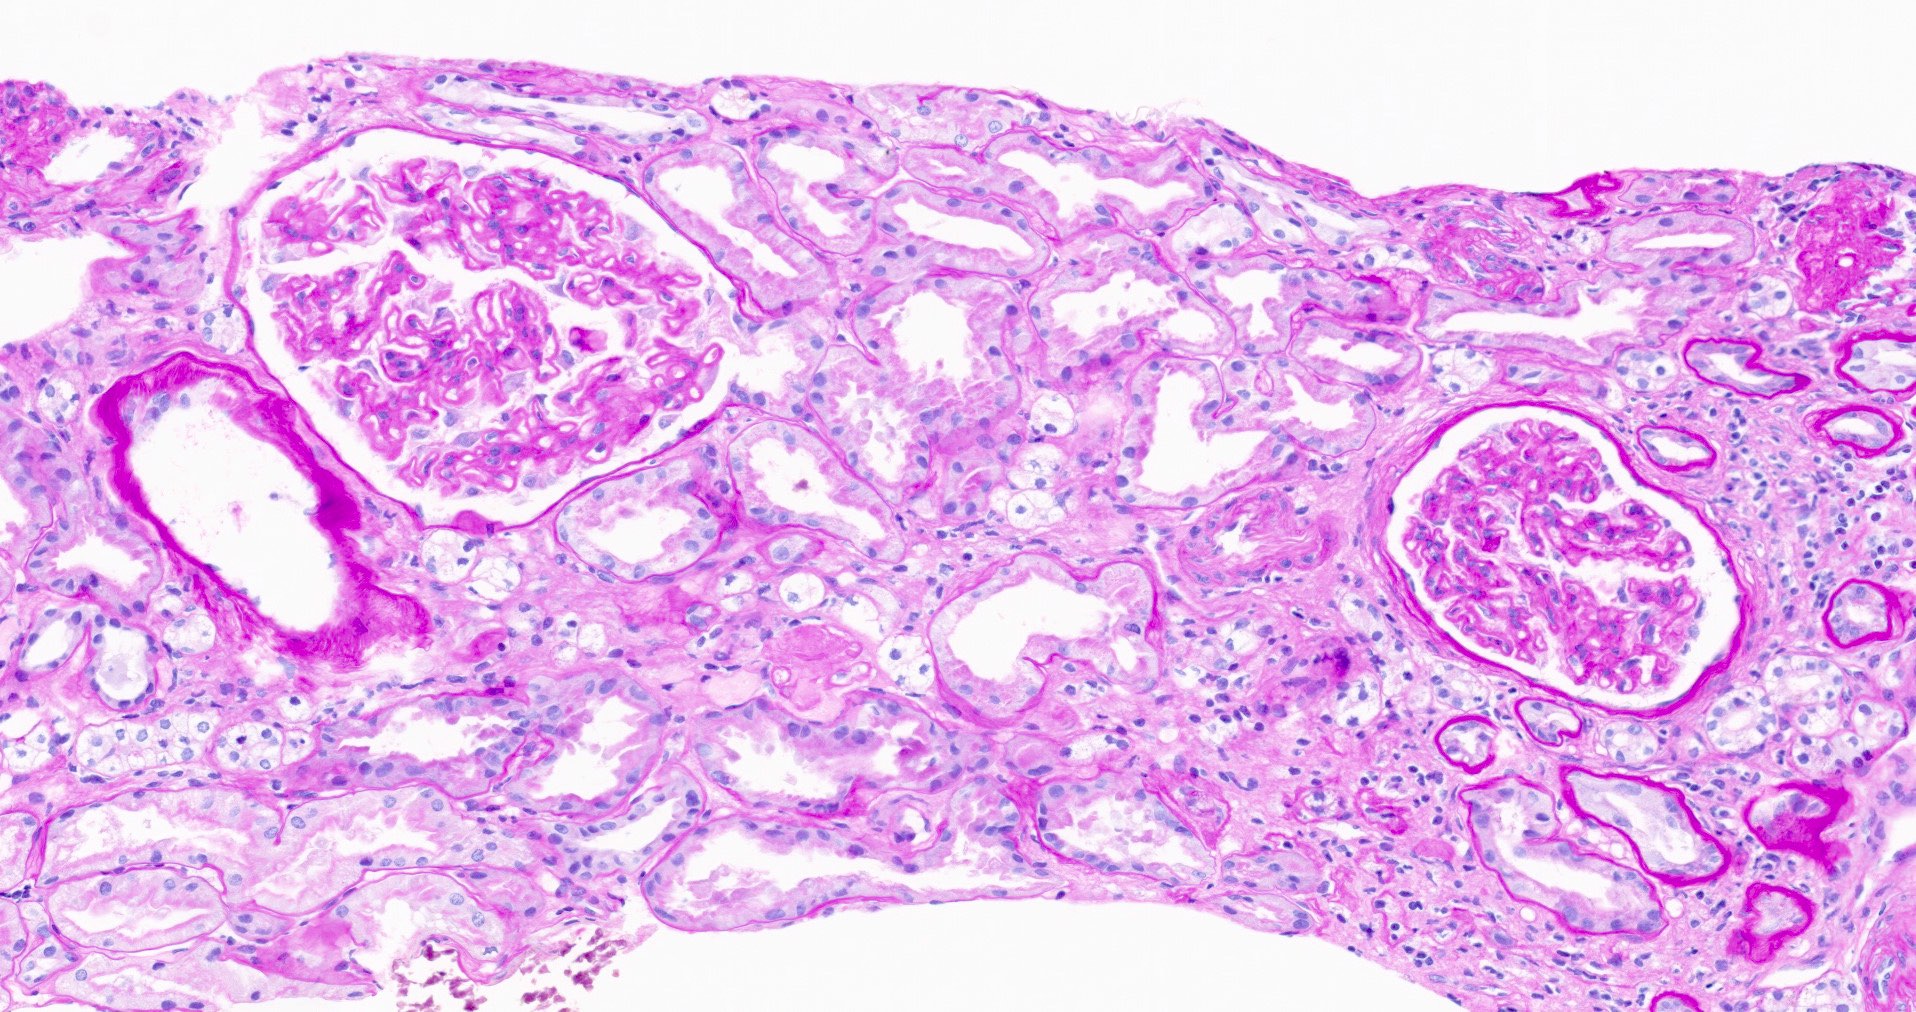

Microscopic (histologic) description

- Glomeruli may appear entirely normal in early disease (stage 1)

- Thickening of glomerular basement membrane

- Subepithelial spike formation or vacuolated appearance on PAS or Jones silver stain (Colvin: Diagnostic Pathology - Kidney Diseases, 2nd Edition, 2015, Zhou: Silva's Diagnostic Renal Pathology, 2nd Edition, 2017)

Microscopic (histologic) images